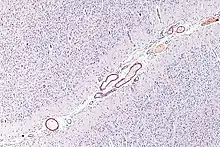

L'AAC résulte du dépôt d'amylose dans la paroi des vaisseaux cérébraux mis en évidence par une coloration au Rouge Congo. La forme d'AAC a plus répandue est l'AAC sporadique β-amyloïde qui résulte du dépôt de peptide Aβ-40 dans la média et l'adventice des artérioles des vaisseaux corticaux ou leptoméningés. Néanmoins, d'autres formes moléculaires ont été décrites (par exemple liées au dépôt de Cystatine C ou de Transthyrétine) dont la fréquence exacte est inconnue en raison de leur grande rareté[5].

Le dépôt du peptide Aβ-40 débute généralement dans la membrane basale externe puis s'étend vers la média des vaisseaux, ce qui cause la dégénération des cellules musculaires lisses qui s'y trouvent. Dans les formes sévères, la média et l'adventice ont disparu et sont remplacées par de la nécrose amyloïde. Seul l'endothelium, paroi la plus fine et la plus interne du vaisseau, reste intacte. Cette forme sévère est souvent associée avec des dilatations microanévrysmales ou des occlusions du vaisseau. On distingue généralement deux formes de AAC selon que les capillaires sont également atteints ou non. En règle générale, l'atteinte prédomine sur la partie postérieure du cerveau et les vaisseaux profonds du cerveau sont respectés[6].